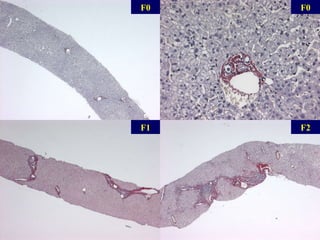

Fibrose

F0 F2 F0 F1

Scores de fibrose cirrhose Nbx ponts fibreux qq ponts fibreux Fibrose portale sans septa Pas de fibrose METAVIR 1994 cirrhose, probable or certaine 6 Nbx ponts fibreux, qq nodules (cirrhose incomplète) 5 Nbx ponts fibreux,  (EP-EP ou EP-CL) cirrhose 4 qq ponts fibreux Ponts fibreux (EP-EP ou  EP-CL) 3 Expansion fibreuse de la plupart des EP 2 Expansion fibreuse de qq EP Fibrose portale sans septa 1 Pas de fibrose Pas de fibrose 0 Ishak 1995 Knodell 1981   Score